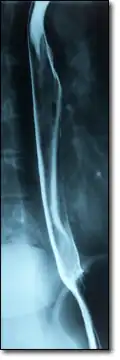

При исследовании печени, поджелудочной железы и жёлчных протоков ведущую роль занимают ультразвуковые исследования (УЗИ), компьютерная томография (КТ) и магнитно-резонансная томография (МРТ). При диагностике состояния пищевода распространено рентгеновское исследование с барием, при котором прохождение глотков бариевой взвеси регистрируется флюороскопически в реальном масштабе времени. Рентгенография пищевода применяется для выявления грыж пищеводного отверстия диафрагмы, опухолей, дивертикулов, стриктур, варикозного расширения вен, инородных тел. Рентгенография или рентгеноскопия с двойным контрастированием или без него применяется при исследовании желудка и двенадцатиперстной кишки с целью выявления язв, опухолей, стриктур, обтураций, контроля результатов оперативных вмешательств. Для диагностики опухолей кишечника, воспалительных заболеваний, причин непроходимости кишки, стриктур, обструкции применяется контрастная рентгенография, компьютерная или магнито-резонансная томография[28].

- Лучевая диагностика болезней ЖКТ

-

Магнито-резонансный томограф

Рентгенография пищевода с контрастной бариевой взвесью -

МРТ-изображение содержащих камни жёлчного пузыря и протоков